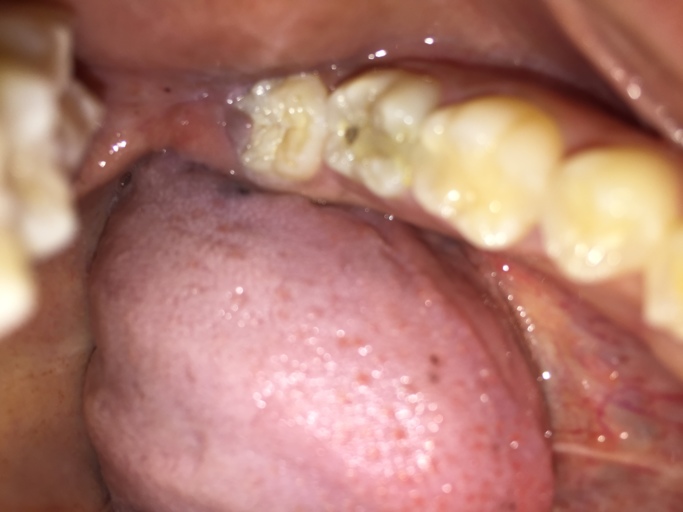

Is this a cavity in my wisdom tooth?

Hi, I am 31 and have observed a dark spot on my lower wisdom tooth (the tooth behind the one with the large silver filling on the picture). All my wisdom teeth have erupted quite good, but short after eruption I had small cavities which were filled...

Is the hole in my tooth a cavity or broken composite filling?

Hello, I have a question about my back molar on the bottom row. I have had white composite fillings as well as sealants in the past years ago. It appears I have a hole in my tooth and it looks as though the filling has broken leaving a nice sized...